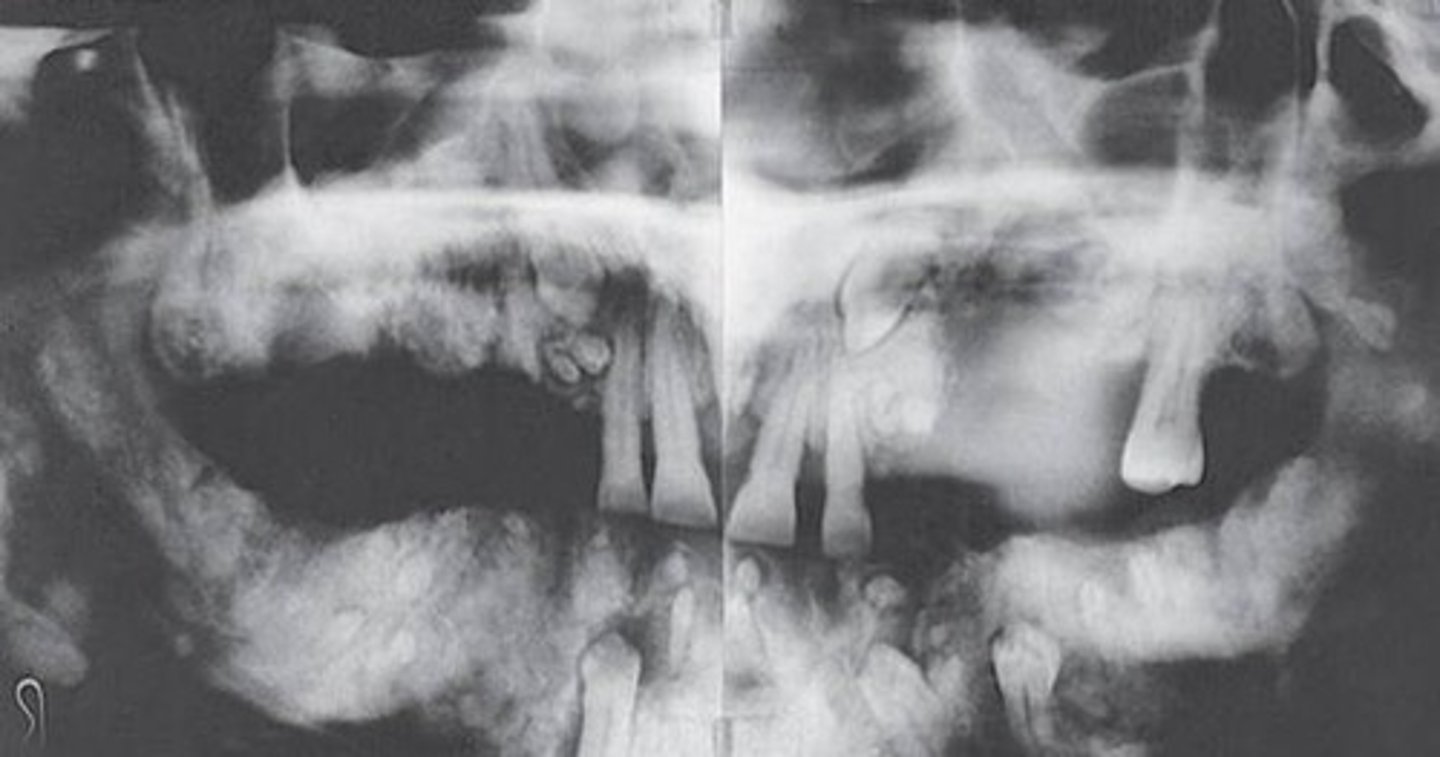

Radiographs of the Cherubism reveals a characteristic of:

soap bubbles or multilocular appearance